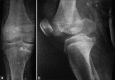

Figure 2

Plain anteroposterior and lateral radiographs were inadequate to define the exact fracture pattern